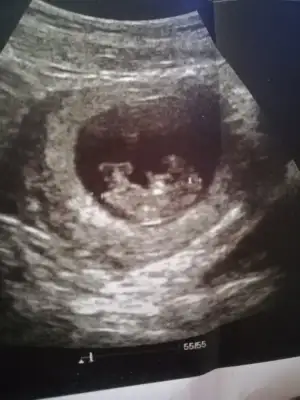

dr soylemeden siz gorun genital nub teorisi ( bebegin cinsiyeti)

Merhaba arkadaşlar 12 haftalık tahminde bulunabilirmisiniz